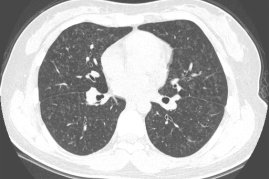

1、所谓急性HP,就是患者接触了较高水平的暴露,例如有患者喜欢饲养鸟类,尤其喜欢宠物鸽子,于是到交易市场去看,在这个过程中,可能出现了间断高水平暴露,于是一些易感个体就在很短的时间内(4到12小时)出现了流感样症状和呼吸道症状,而肺内则出现了一些磨玻璃影。

2、也有一些患者急性发作伴发热,劳力性呼吸困难、乏力和咳嗽,影像表现为小叶中央性的弥漫性的腺泡结节,称之为亚急性HP

3、还有些患者持续性低水平暴露,起病很隐匿,当我们发现时,已经出现了劳力性呼吸困难,干咳,体重减轻和乏力,而影像出现了既有磨玻璃影,也有肺纤维化的表现,称之为慢性HP

图:(从左至右)急性、亚急性、慢性